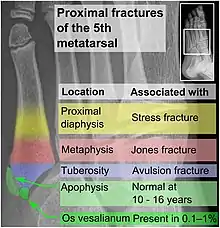

- Proximal diaphysis, typically stress fracture.[12][13]

- Metaphysis: Jones fracture[14]

-Tuberosity: Pseudo-Jones fracture[15] (avulsion fracture).[15]

Normal anatomy:

- Apophysis: Normal at 10 - 16 years.[16]

- Os vesalianum, an accessory bone.[17]

Other proximal fifth metatarsal fractures exist, although they are not as problematic as a Jones fracture. If the fracture enters the intermetatarsal joint, it is a Jones fracture. If, however, it enters the tarsometatarsal joint, then it is likely an avulsion fracture caused by pull from the fibularis brevis tendon. An avulsion fracture at the base of the fifth metatarsal is sometimes called a "dancer's fracture" or a "pseudo Jones fracture", and usually responds readily to non-operative treatment.[18] The X-ray appearance of the developmental "apophysis" in this area may have some resemblance of a fracture, but is not a fracture; it is the secondary ossification center of the metatarsal bone. It is a normal finding that occurs at this site in adolescents.[19] If an injury to that area has occurred, the physician is often able to interpret certain radiographic clues to make the differentiation. An avulsion fracture at this location is typically extra-articular and oriented transversally as compared to the longitudinal orientation of an unfused apophysis.[19]